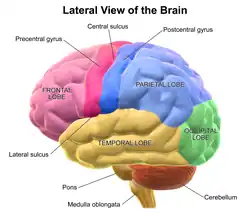

Model images

Lateral view of left hemisphere.

Lateral view of left hemisphere. -

The lobes of the brain are the four major identifiable regions of the human cerebral cortex, and they comprise the surface of each hemisphere of the cerebrum.[1] The two hemispheres are roughly symmetrical in structure, and are connected by the corpus callosum. Some sources include the insula and limbic lobe but the limbic lobe incorporates parts of the other lobes. The lobes are large areas that are anatomically distinguishable, and are also functionally distinct. Each lobe of the brain has numerous ridges, or gyri, and furrows, sulci that constitute further subzones of the cortex.[2] The expression "lobes of the brain" usually refers only to those of the cerebrum, not to the distinct areas of the cerebellum.

Frontal lobe

The frontal lobe is located at the front of each cerebral hemisphere and positioned in front of the parietal lobe and above and in front of the temporal lobe. It is separated from the parietal lobe by a space between tissues called the central sulcus, and from the temporal lobe by a deep fold called the lateral sulcus, also called the Sylvian fissure. The precentral gyrus, which forms the posterior border of the frontal lobe, contains the primary motor cortex (area 4 under the Brodmann area architecture) which controls voluntary movements of specific body parts. The precentral region also contains the premotor cortex (Brodmann area 6).

Parietal lobe

Occipital lobe

Temporal lobe